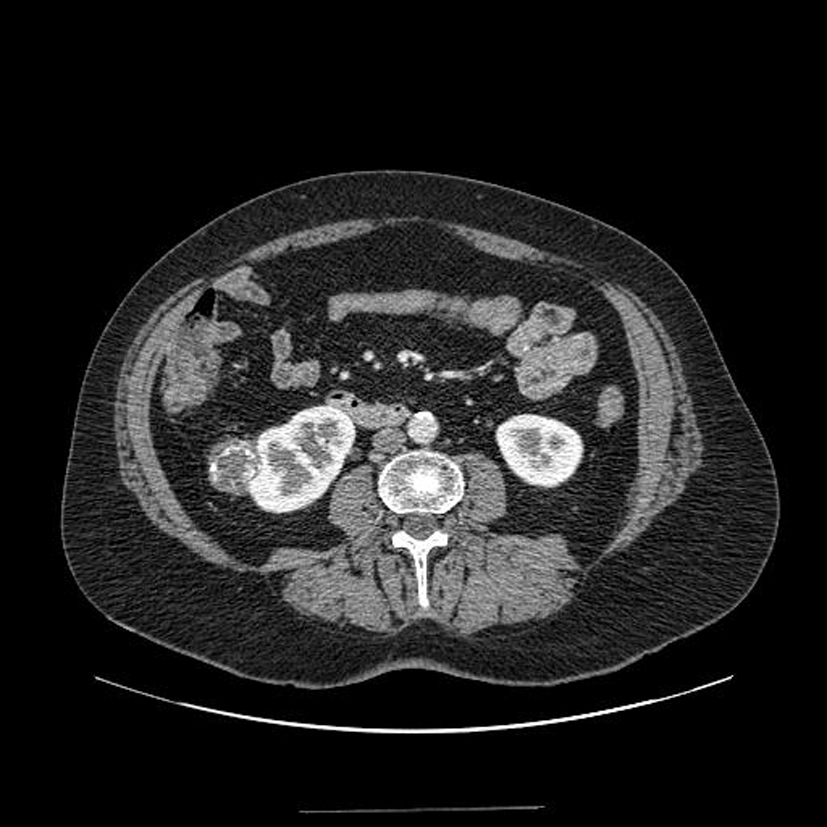

Diagnostic?

Tumeur rénale droite avec thrombus de la veine rénale